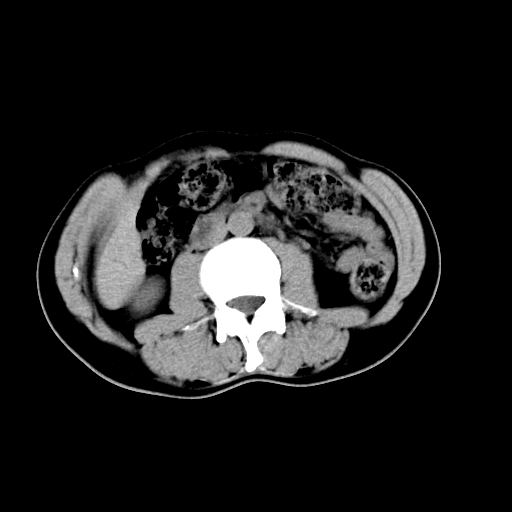

男,47岁,左输尿管结石碎石治疗后10余日。彩超示:左输尿管下段狭窄、输尿管积水。请各位讨论一下左输尿管下段结石还是静脉石?

两侧髂总动脉壁斑状及点状钙化.左侧输尿管行经与左髂总动脉相交后见高密度影,且下段输尿管管腔未见扩张,应该要考虑结石伴以上输尿管及肾盂积水.但右侧结节状高密度影,也应该是结石吧!那以上输尿管未见扩张呢!因此静脉结石可能性也较大.请问楼主碎石前左侧输尿管结石位置.

虽左侧有轻度肾盂积水但不支持结石。1结石边周应该有软组织包绕呈晕征。2钙化点前面见输尿管影也不支持是结石。3彩超没提结石。建议超生复查。

输尿管先位于腹部,后进入盆腔,最后斜穿膀胱壁开口于膀胱,因此,临床上常将输尿管分为腹段、盆段和壁内段。第1个狭窄:在肾盂与输尿管移行处。第2个狭窄:在跨过髂血管处。第3个狭窄:在穿过膀胱壁处。这些狭窄是结石容易滞留的部位。

左侧输尿管有轻度扩张伴有肾盂积水,输尿管下段周围的高密度影不象在输尿管内。

同意,不支持结石。(因显示该高密度影前见扩张输尿管影,另外两侧对称显示)。

左侧高密度影在左侧输尿管的内侧方,所以不考虑输尿管结石.

我认为不是结石的可能性大,因为他的位置和血管钙化的位置邻近